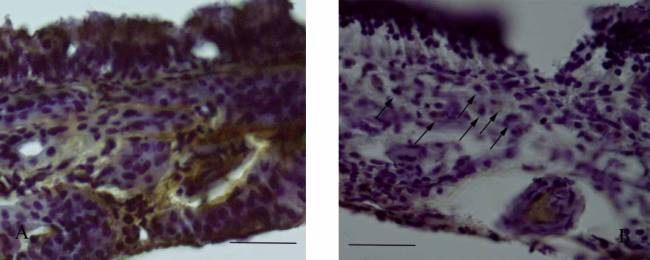

Изменение активности тканевого ингибитора ММР9

(TIMP2), демонстрирует при длительной экспозиции табачного дыма противоположную

динамику (см. табл.). В группе курильщиков во всех слоях слизистой оболочки

заметно сокращается активность TIMP2-позитивной зоны, однако в собственной пластинке

слизистой обнаруживаются сгруппированные в небольшие кластеры макрофаги,

демонстрирующие невысокий уровень TIMP2 (рис. 2Б - указаны стрелками).

Рисунок

2. Распределение иммуногистохимической активности TIMP2 в тканях слизистой

оболочки носа крыс контрольной группы (А) и группы курильщиков (Б). На рисунке

Б стрелками указаны TIMP2 – иммунопозитивные макрофаги. Масштаб

100мкм.